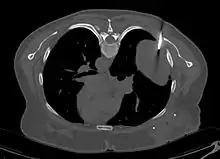

- Tumeur fibreuse solitaire du rein

Aspect tomodensitométrique. La tumeur est repérée par les flèches[46].